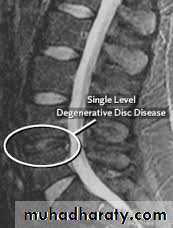

CHRONIC INTERVERTEBRAL DISC DEGENERATIONMRI:

Bulging of the annulus fibrosus in both sagittal and axial projections and diminished thickness and reduced signal intensity (dehydration) of the degenerating disc.

CHRONIC INTERVERTEBRAL DISC DEGENERATION

This is an age related phenomenon that occurs in over 80 per cent of people who live for more than 50 years and in most cases it is asymptomatic.CHRONIC INTERVERTEBRAL DISC DEGENERATION